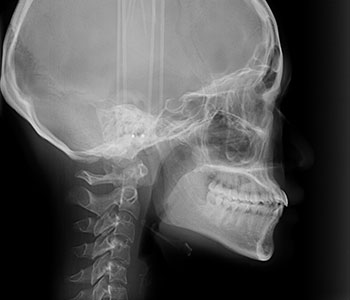

セファロ

主に矯正治療で使用する横顔のレントゲンです。骨格や歯の傾きが分かります。

頭の骨や顎の骨、前歯の位置など様々な角度から調べることができます。